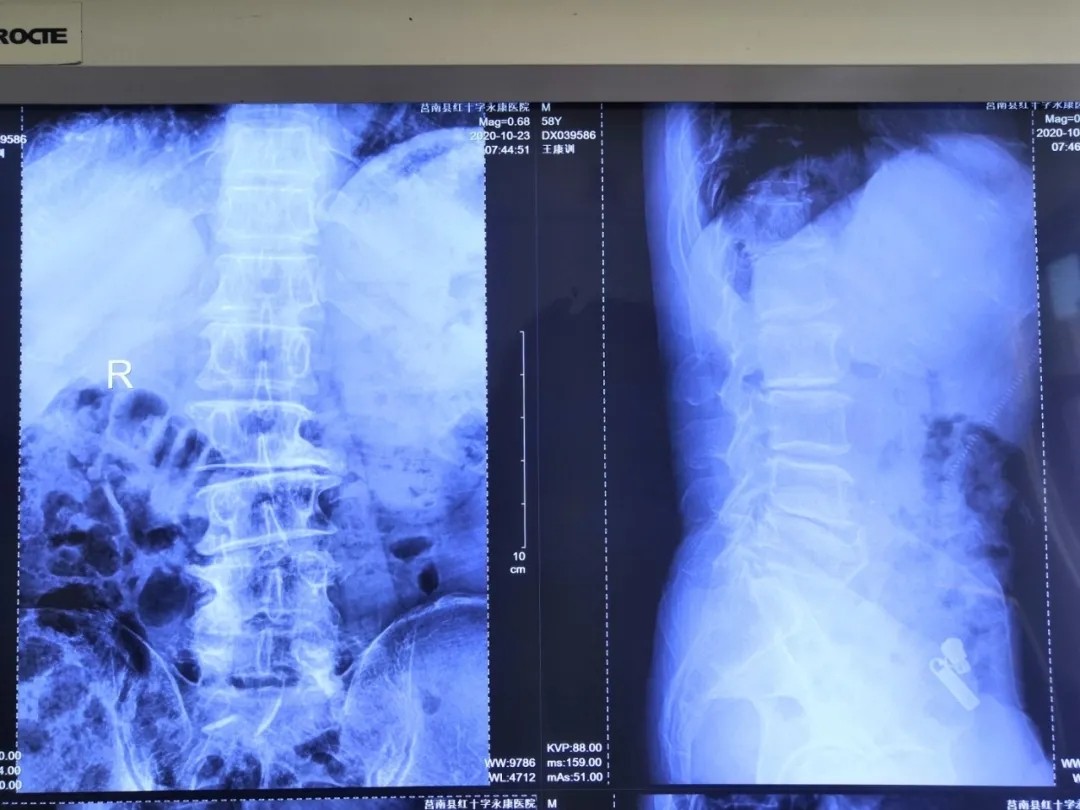

影像資料:

診 斷:

腰椎管狹窄癥;腰椎間盤突出癥;老年退變性側彎。

術后影像: